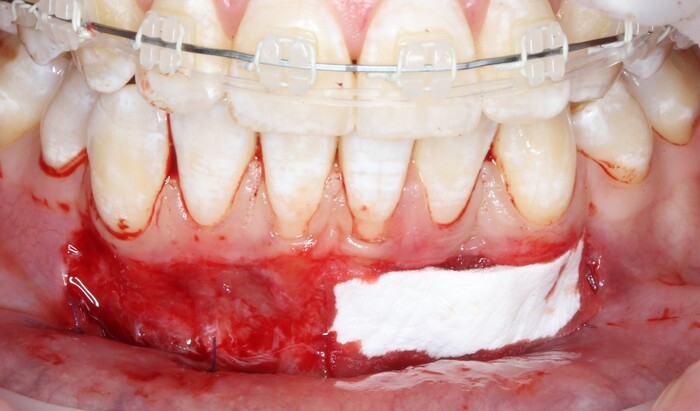

2 – проведение пластики десны.

Был взят трансплантат в области бугра верхней челюсти (это то место, где раньше был зуб мудрости).